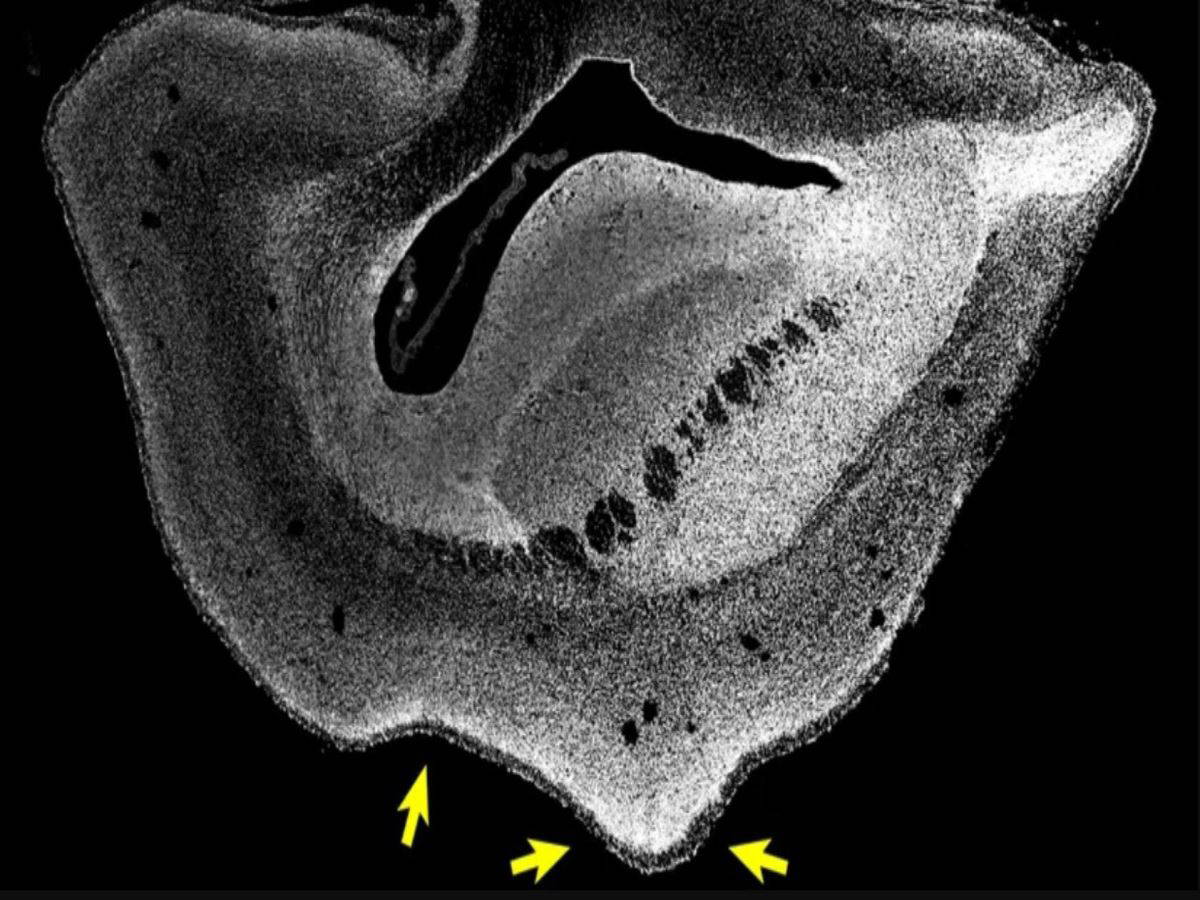

Oklar, insan geni verilmiş 101 günlük marmoset beynindeki katlanmaları gösterir / Science

- Maymun beynini katlanma biçimini, insan beyninin katlanma biçimine benzer hale getirdi.